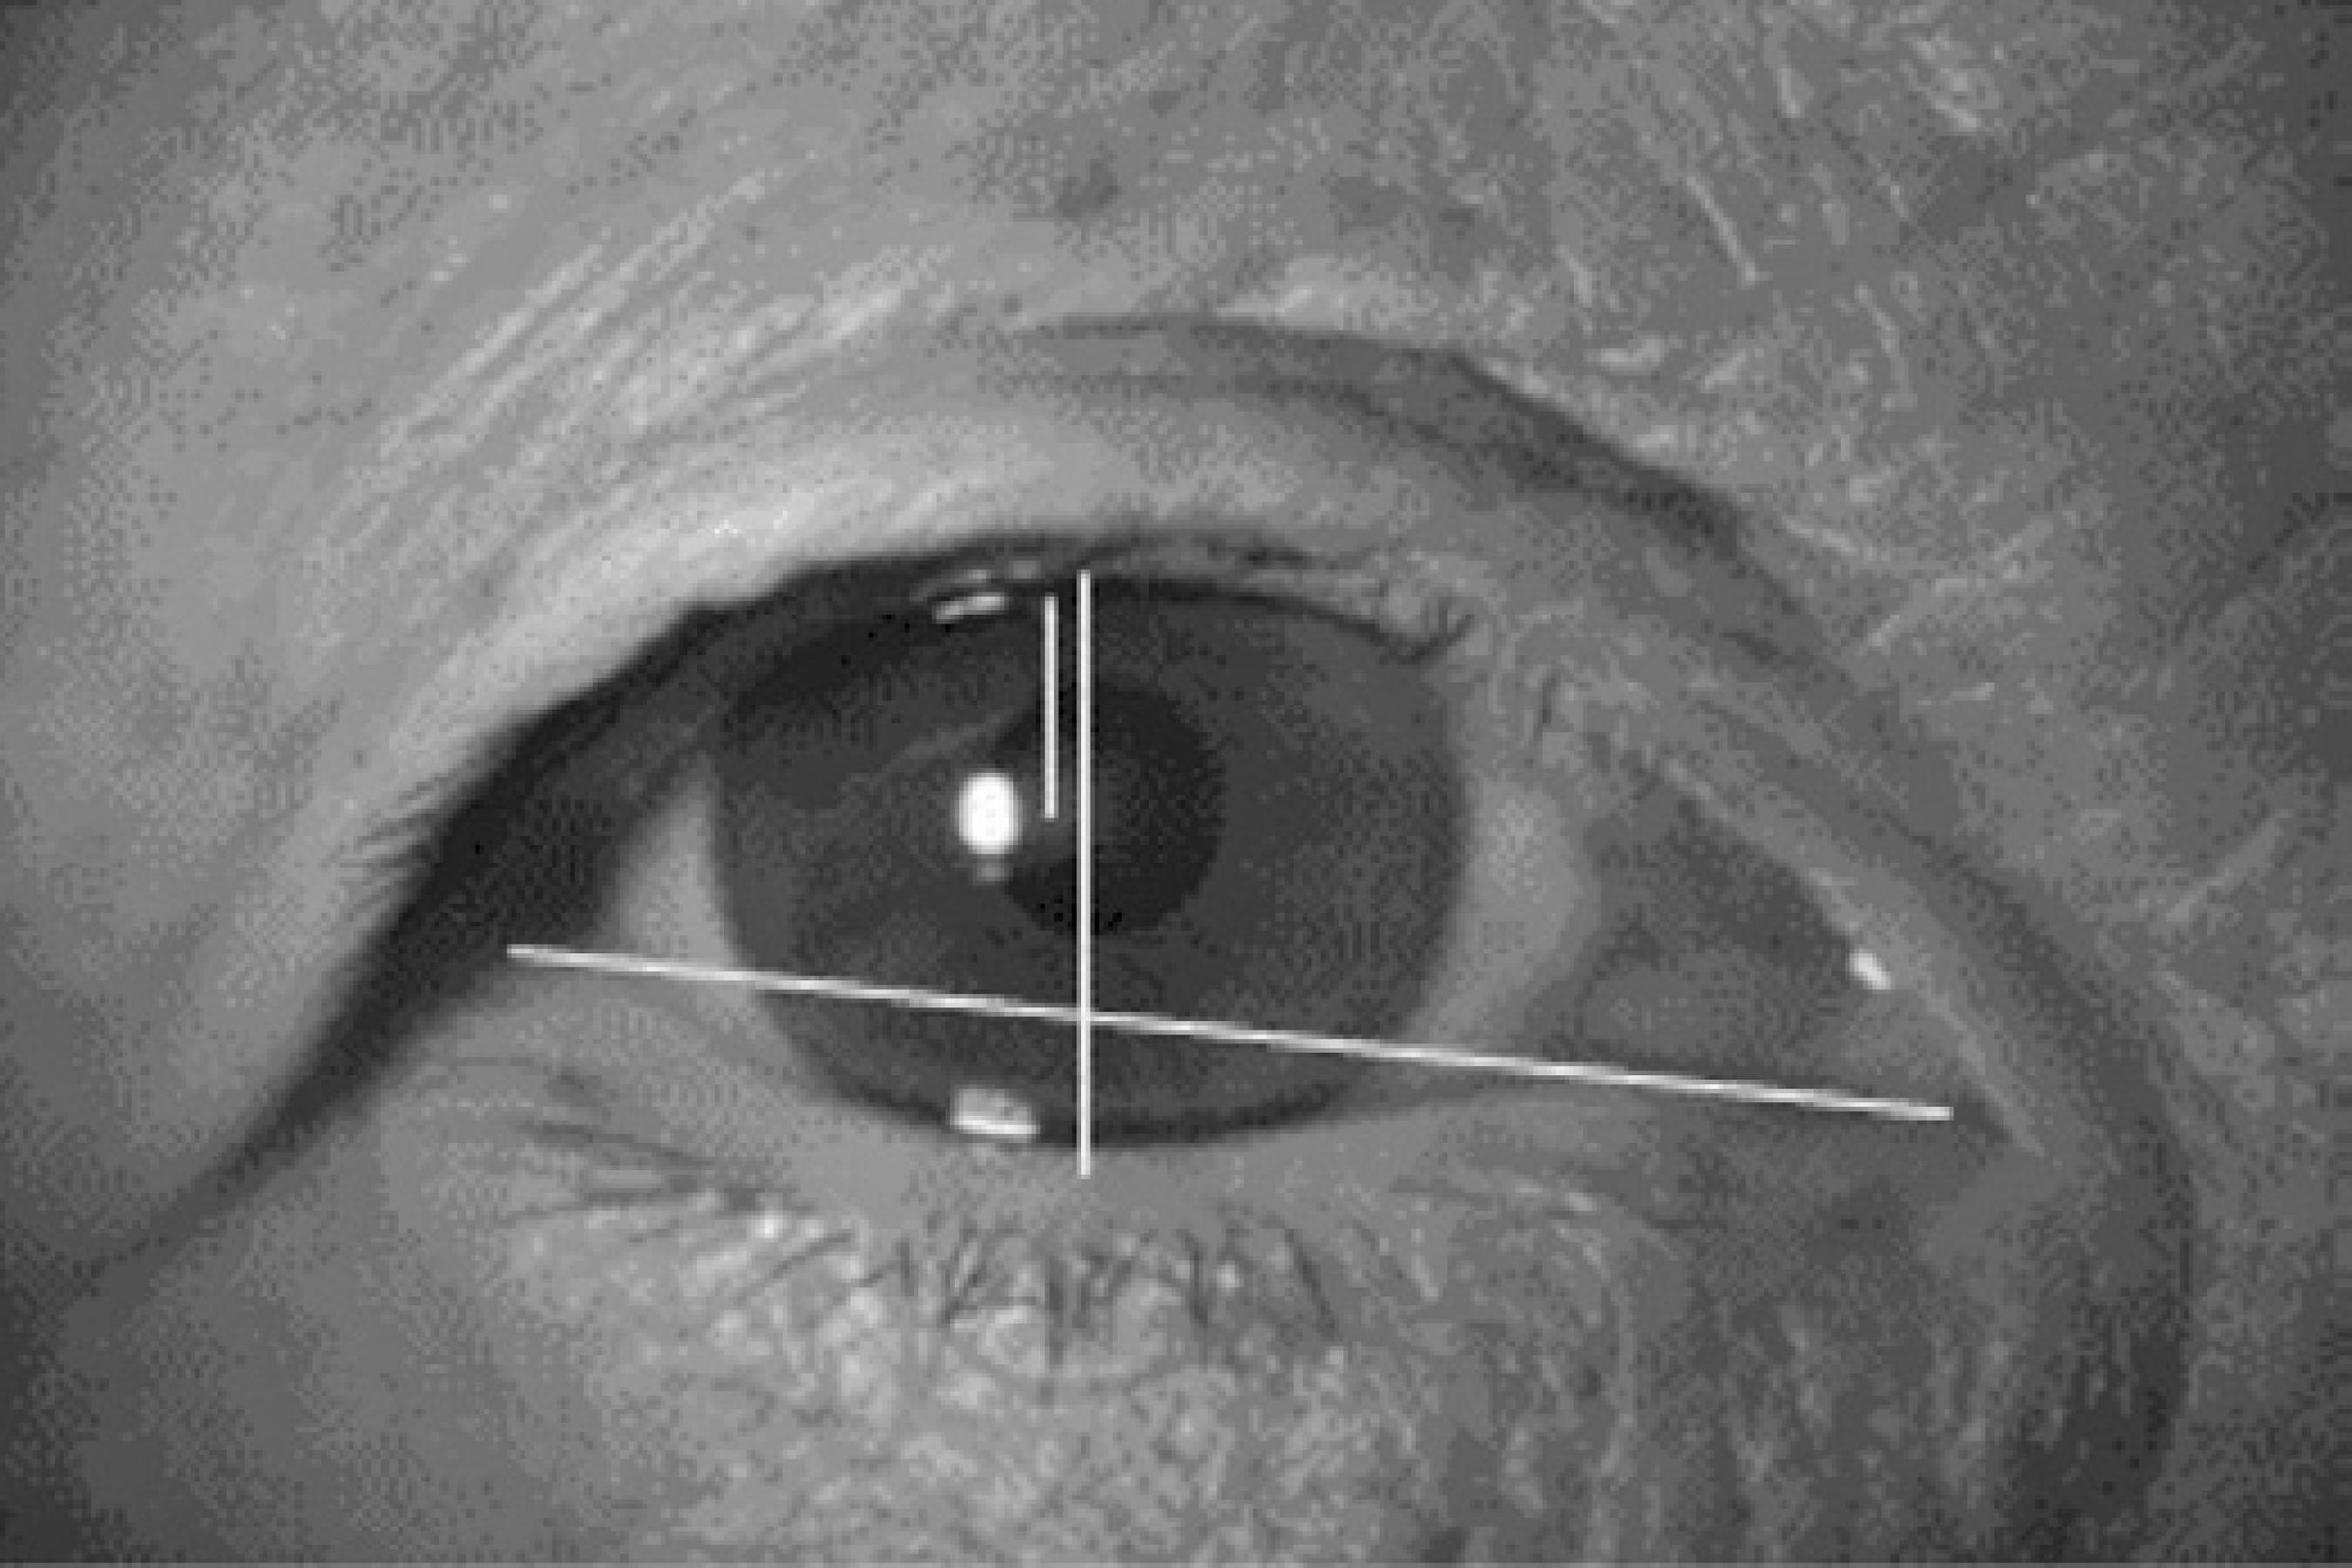

Images were obtained with a Nikon® Coolpix 4100 digital camera and flash in frontal view 30 cm from the subject’s face. The subject was opposite to and at the same eye level as the examiner. The images were obtained with the eyes in the primary position and with the gaze at the center of the examiner’s nose to obtain clear photographs of both eyes. The images were then transferred to a computer running Windows and processed by Scion Imaging Software® (Scion Corporation, USA). The following parameters were measured and evaluated (Figure 1): fissure width: the distance between the medial canthus and the lateral canthus obtained by a line linking the lateral and medial corners of the eyelids; fissure height: the distance between the upper eyelid margin and the lower eyelid margin with open eyes obtained by a line linking the upper and lower eyelid margins and passing through the pupil; margin reflex distance (MRD): the perpendicular distance between the highest point of the open upper eyelid margin and the pupil reflex (MRD1), and the distance between the margin of the inferior eyelid margin to the pupil reflex (MRD2).

Figure 1 Representation of the width dimension of the palpebral fissure, obtained by a line linking the lateral and medial corners; the height dimension was obtained by a line linking the superior and inferior palpebral eyelid and passing through the pupil; MRD1 reflecting the distance between the open upper eyelid margin and the pupil reflex; MRD2 is the difference between the height and the MRD1